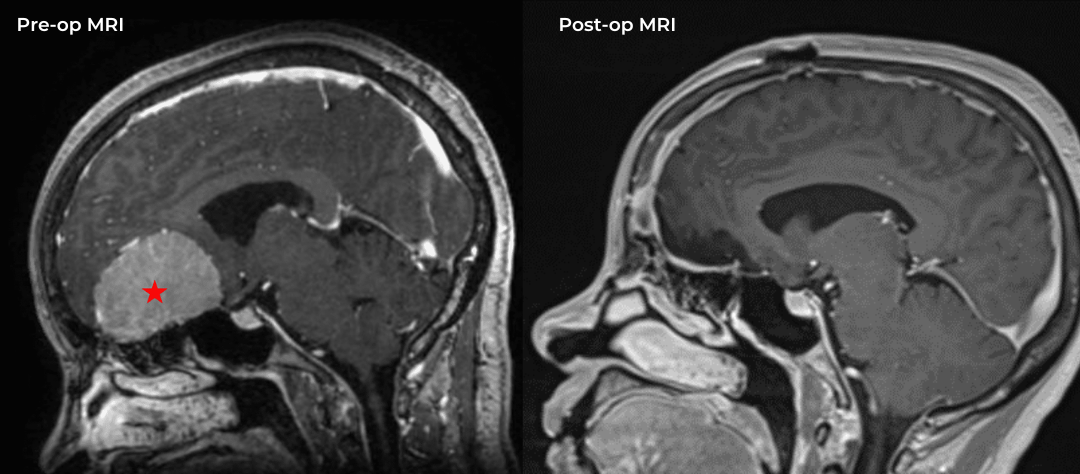

Fig. 2 – Pre-operative imaging shows multiple areas of most likely embolic stroke in the right corona radiata.

MRI imaging using the diffusion-weighted image sequence, which is highly sensitive for acute stroke showed multiple areas of most likely embolic stroke in the right frontal white matter (Figure 1) as well as the right corona radiata (Figure 2).